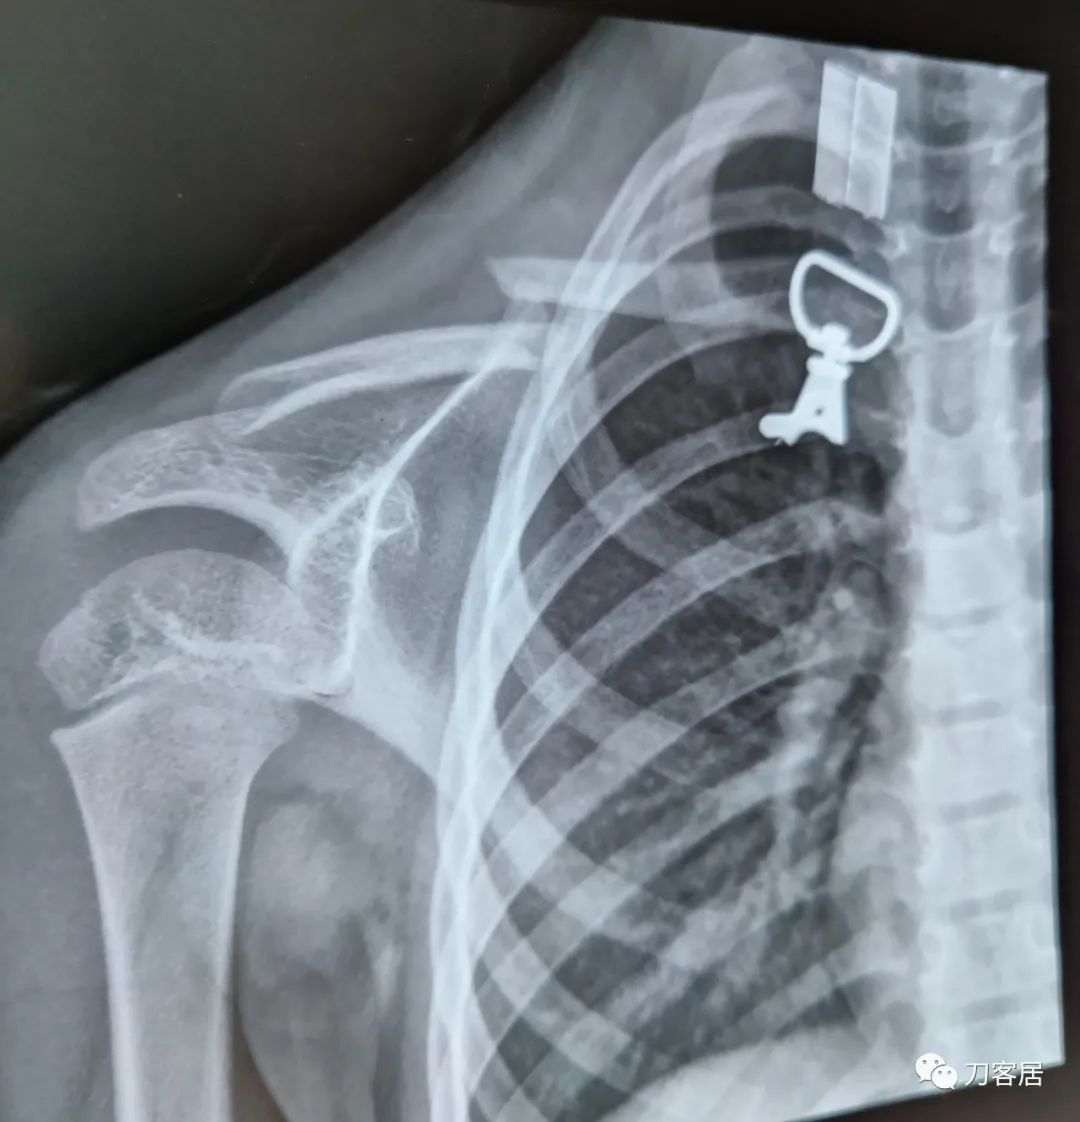

大家都很敬业苦口婆心,奈何家属可能不理解,我提供个反面教材给看看手术失败病例,也让家属感受一下。

网络问诊的病例,没有后续,但觉得孩子很无辜!

为啥要急着拔针?针留在皮外?

网络问诊的病人,我也不知道那个医院为啥要这么快拔针[难过],应该是术后8周,见骨痂生长,皮外针尾也有刺激,就考虑拔针了。

目前这个病人从片子上看确实得要植骨了,骨不连很明显了,髓腔断端看上去也很圆滑,似乎已经闭合了[捂脸]。

儿童锁骨骨折罕见不愈合,这个孩子锁骨骨折不愈合,与手术广泛剥离,骨膜损伤有关系。

应该是切开复位的,克氏针的尖都去掉了,闭合复位就很难穿进去,只是不知道剥离了多少。

看术后片子,术者可能是切开手术。